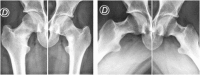

Bilateral concomitant femoral neck stress fracture in a sedentary patient with anorexia nervosa

A 27 years old sedentary woman presented bilateral femoral neck stress fractures after having clinically recovered from anorexia nervosa and was treated with bilateral internal fixation.

Conclusion: Although light exercise is usually considered after recovery from anorexia nervosa to improve bone quality, this case of a sedentary patient suggests that weight gain, per se, could increase the stress fracture risk. Because of the physiological and psychological characteristics, these patients should be treated with a multi-disciplinary approach.